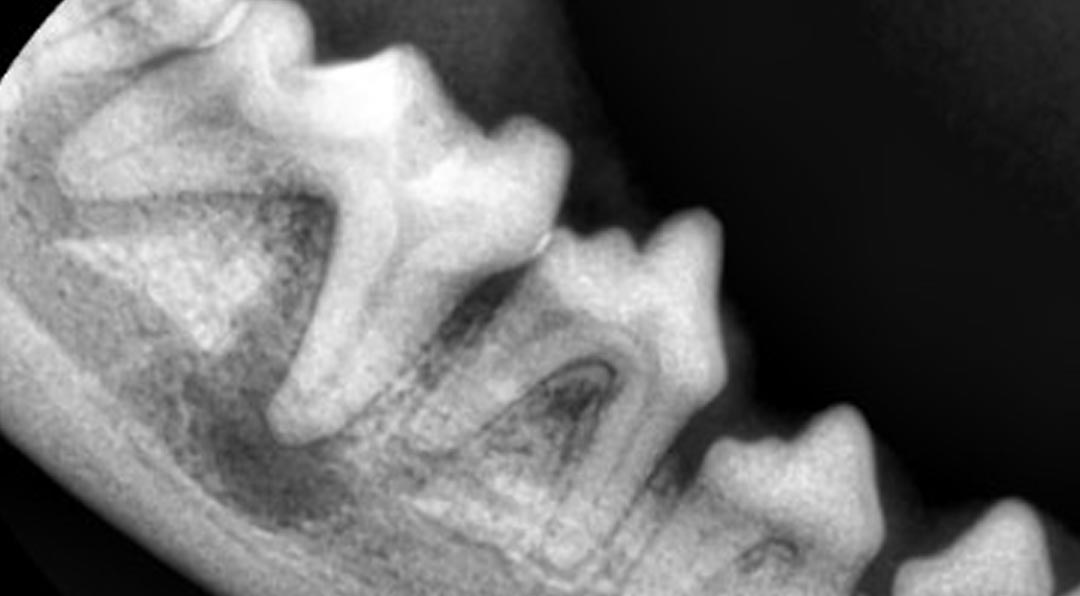

디지털 덴탈 엑스레이, CT 기반 구강 정밀 진단 가능

치과 클리닉은 반려동물의 치아, 치주조직, 구강점막 등 구강 전반의 건강을 진단하고 치료하는 전문 진료과입니다. 강아지와 고양이 모두 3세 이상이 되면 약 80% 이상이 치주 질환을 경험하게 되며, 이는 전신 질환으로도 이어질 수 있어 정기적인 치과 진료가 매우 중요합니다. 치과 클리닉에서는 스케일링, 발치, 치주수술, 교합 이상, 턱뼈 문제까지 종합적인 진료를 제공합니다.